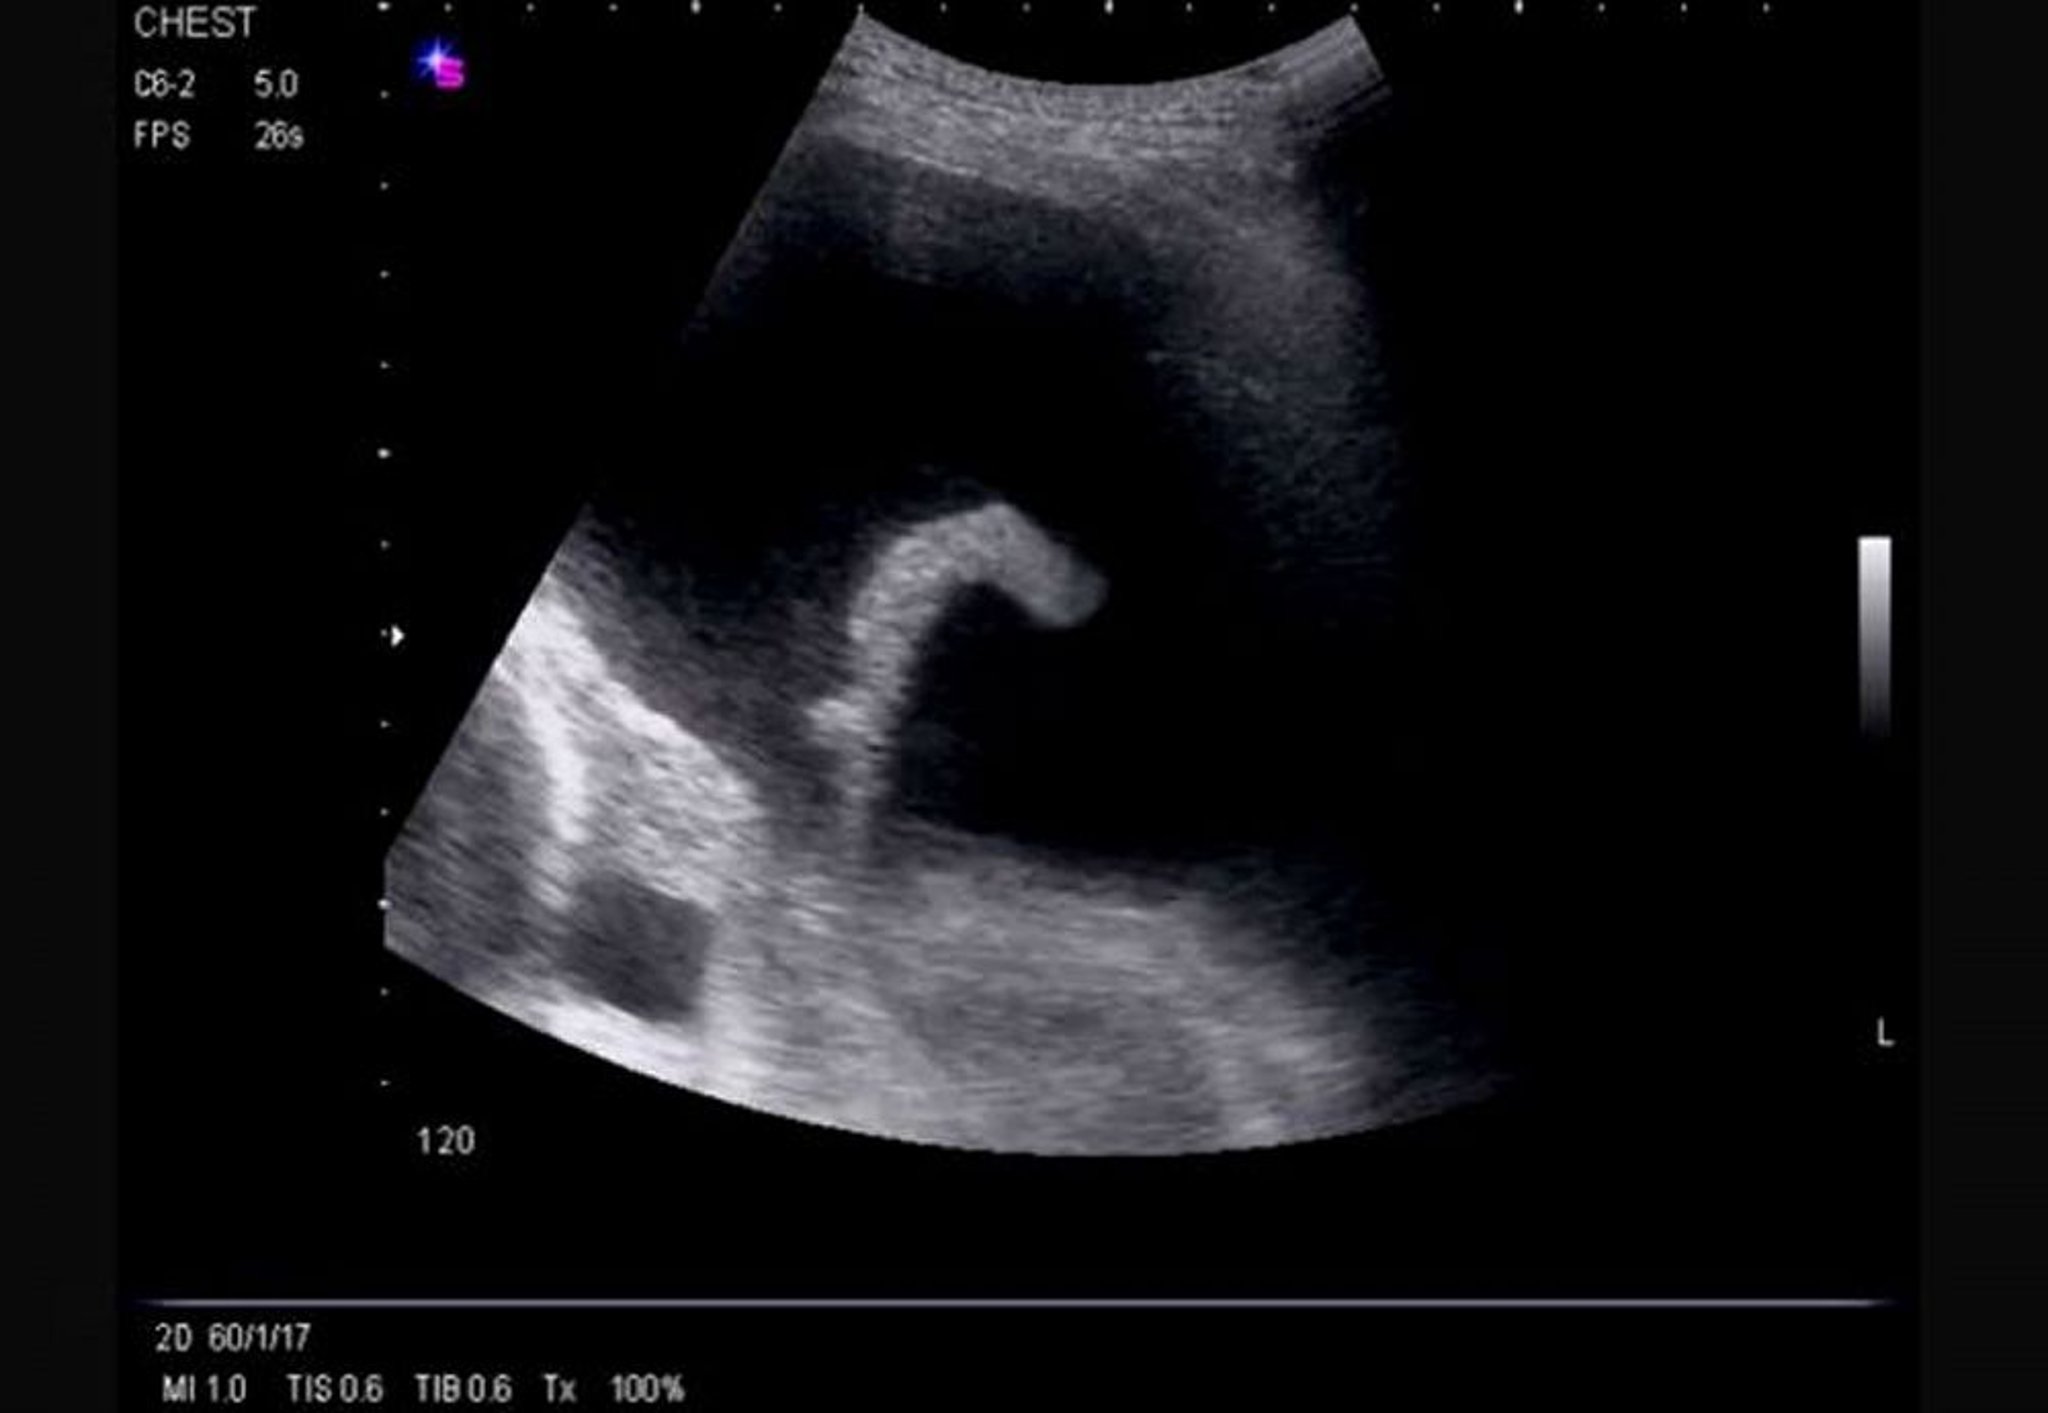

Lateral Thoracic Ultrasound (Left)

This ultrasound shows a large, left-sided, free-flowing effusion causing compressive left lower lobe atelectasis and revealing the left ventricle.

Image courtesy of Najib M. Rahman, BMBCh MA (oxon) DPhil.